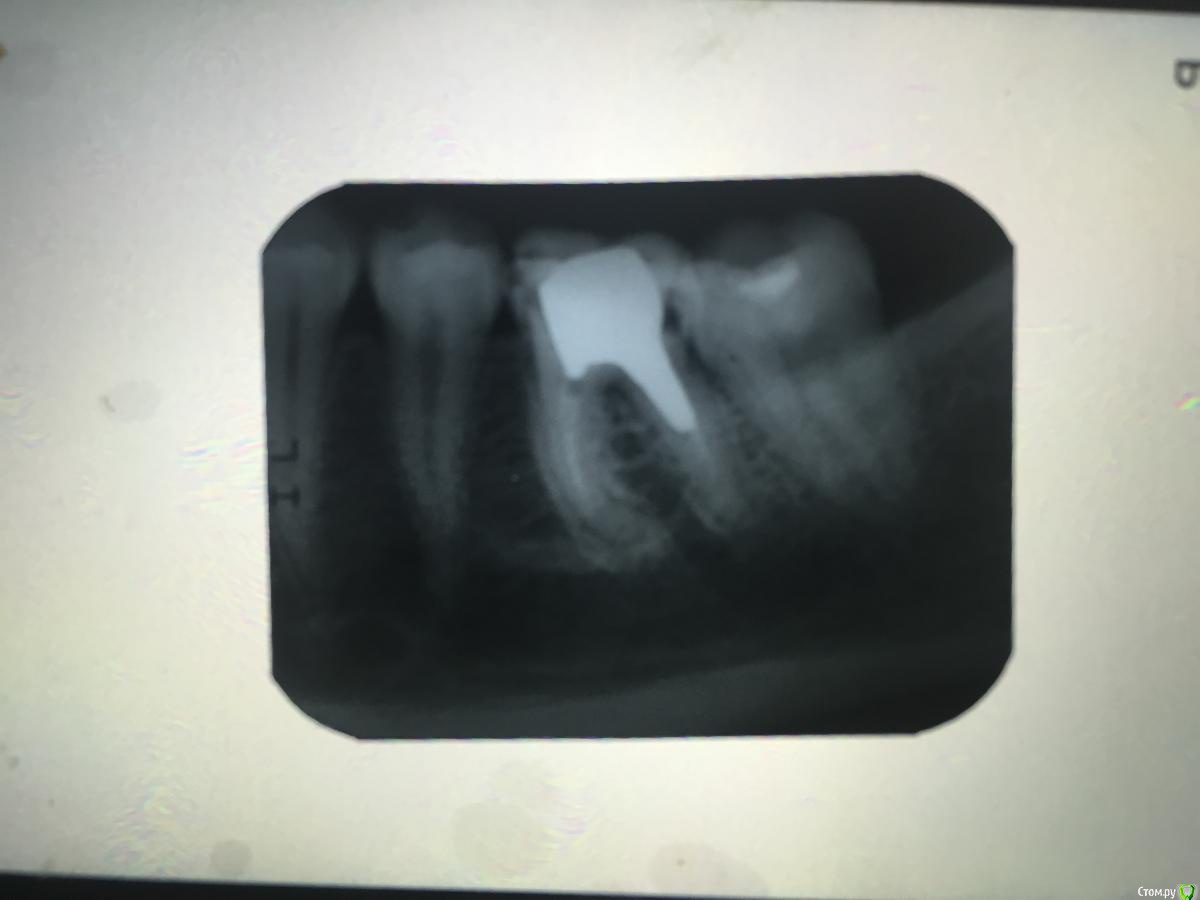

Денис777 Опубликовано 25 марта, 2015 Поделиться Опубликовано 25 марта, 2015 Доктора как по вашему мнению удалять 36 или попытаться вызвонить вкладку....?Об-но: Острая ноющая боль,боли при накусывании....(Боли по типу периодонтита) Ссылка на комментарий

Гарриевич Опубликовано 25 марта, 2015 Поделиться Опубликовано 25 марта, 2015 нужно учитывать, что дистальный канал щелевидный и мы на этом снимке можем видеть как раз такую проекциюя бы вкладку убрал и перебрал зуб) 1 Ссылка на комментарий

Гарриевич Опубликовано 25 марта, 2015 Поделиться Опубликовано 25 марта, 2015 если есть страх, что при извлечении вкв можете повредить корень, отдайте коллгам, пусть вынимаютв остальном нормальный зуба кариес корня в любом случае нужно подтвердить клинически Ссылка на комментарий

Денис777 Опубликовано 25 марта, 2015 Автор Поделиться Опубликовано 25 марта, 2015 Потому,что дистальный корень этого зуба разрушен до уровня кости .. Ссылка на комментарий

Bratok Опубликовано 26 марта, 2015 Поделиться Опубликовано 26 марта, 2015 С этим зубом можно сделать многое, но эндодонтический и реставрационный прогноз неблагоприятный по данному снимку.Обычно для того, чтобы дать долгосрочный прогноз нужно смотреть динамику после всех лечебных мероприятий. 6-8 месяцев, потом через 2-4 года. Ссылка на комментарий

voff Опубликовано 26 марта, 2015 Поделиться Опубликовано 26 марта, 2015 и маленькое темное пятнышко по фуркации скорее станет большой проблемой в дальнейшем Ссылка на комментарий

Гарриевич Опубликовано 26 марта, 2015 Поделиться Опубликовано 26 марта, 2015 Доктора, это де прицельный снимок на пленке снятый на телефон))Как по такому снимку можно зуб однозначно на удаление посылать Ссылка на комментарий

Larnary Опубликовано 26 марта, 2015 Поделиться Опубликовано 26 марта, 2015 А мне крайне не нравится дистальный корень на контакте с 37. Конечно можно сделать КТ данной области,но чувствую прогноз будет неблагоприятный Ссылка на комментарий

Megadeth Опубликовано 26 марта, 2015 Поделиться Опубликовано 26 марта, 2015 я бы удалял. но как вариант извлечь вкладку, удалить дистальный корень, перепломбировать мед. каналы, новая вкладка и коронка с подвесом. Ссылка на комментарий